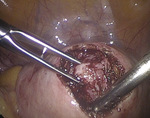

Po wytworzeniu odmy otrzewnej wprowadzono przez pępek trokar 10 mm, a następnie optykę laparoskopu i trokary dodatkowe w podbrzuszu 5 i 10 mm. Pacjentkę ułożono w pozycji Trendelenburga. Uwidoczniono powiększony trzon macicy, ścianę przednią uwypukloną przez mięśniak śródścienny o średnicy około 4-5 cm (ryc. 1), przydatki obustronnie bez zmian. Pozostałe narządy jamy otrzewnej dostępne wizualizacji laparoskopowej były niezmienione.